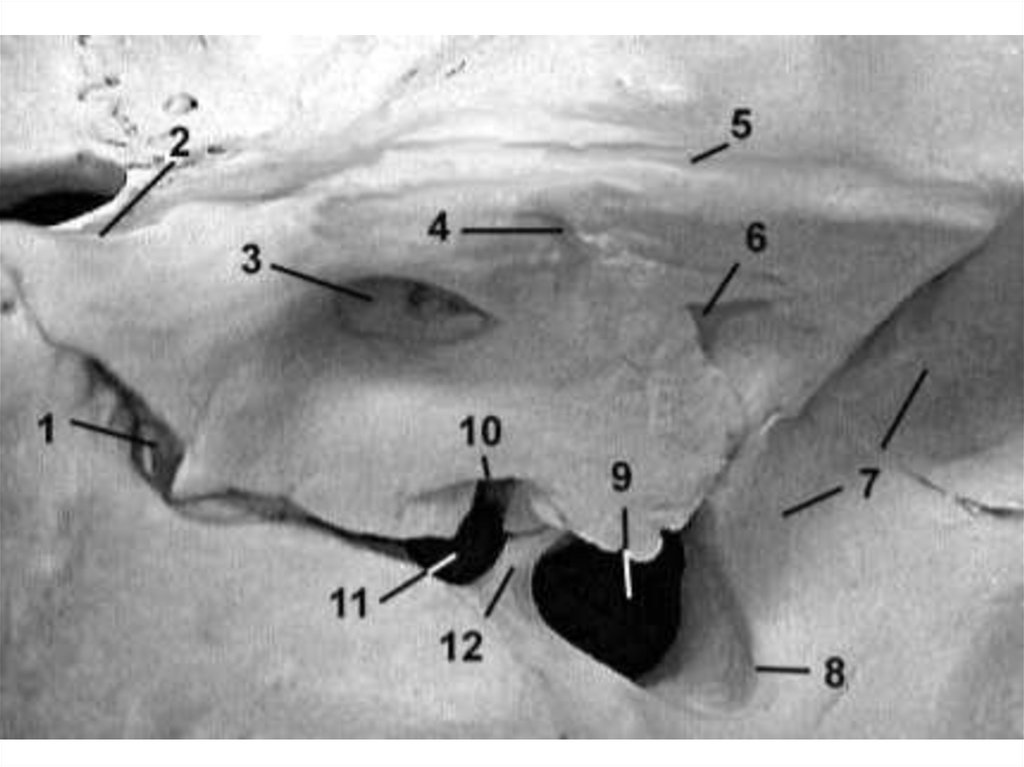

ОВАЛЬНОЕ ОТВЕРСТИЕ

Содержимое:

• нижнечелюстной нерв;

• венозное сплетение овального отверстия;

• добавочная ветвь от средней менингеальной артерии.

ВЕНОЗНОЕ ОТВЕРСТИЕ

ОСТИСТОЕ ОТВЕРСТИЕ

• средняя менингеальная артерия + вены;

• менингеальная ветвь нижнечелюстного нерва.

КАНАЛ АРНОЛЬДА

• Малый каменистый нерв.

РВАНОЕ ОТВЕРСТИЕ

• внутренняя сонная артерия;

• большой каменистый нерв;

• симпатические нервы от сонного сплетения.

РАСЩЕЛИНА КАНАЛА БОЛЬШОГО КАМЕНИСТОГО

НЕРВА

большой каменистый нерв;

каменистая ветвь средней менингеальной артерии.

БОРОЗДА БОЛЬШОГО КАМЕНИСТОГО НЕРВА

• Большой каменистый нерв.

РАСЩЕЛИНА КАНАЛА МАЛОГО КАМЕНИСТОГО НЕРВА

малый каменистый нерв;

верхняя барабанная артерия.

БОРОЗДА МАЛОГО КАМЕНИСТОГО НЕРВА

КАМЕНИСТАЯ ЩЕЛЬ